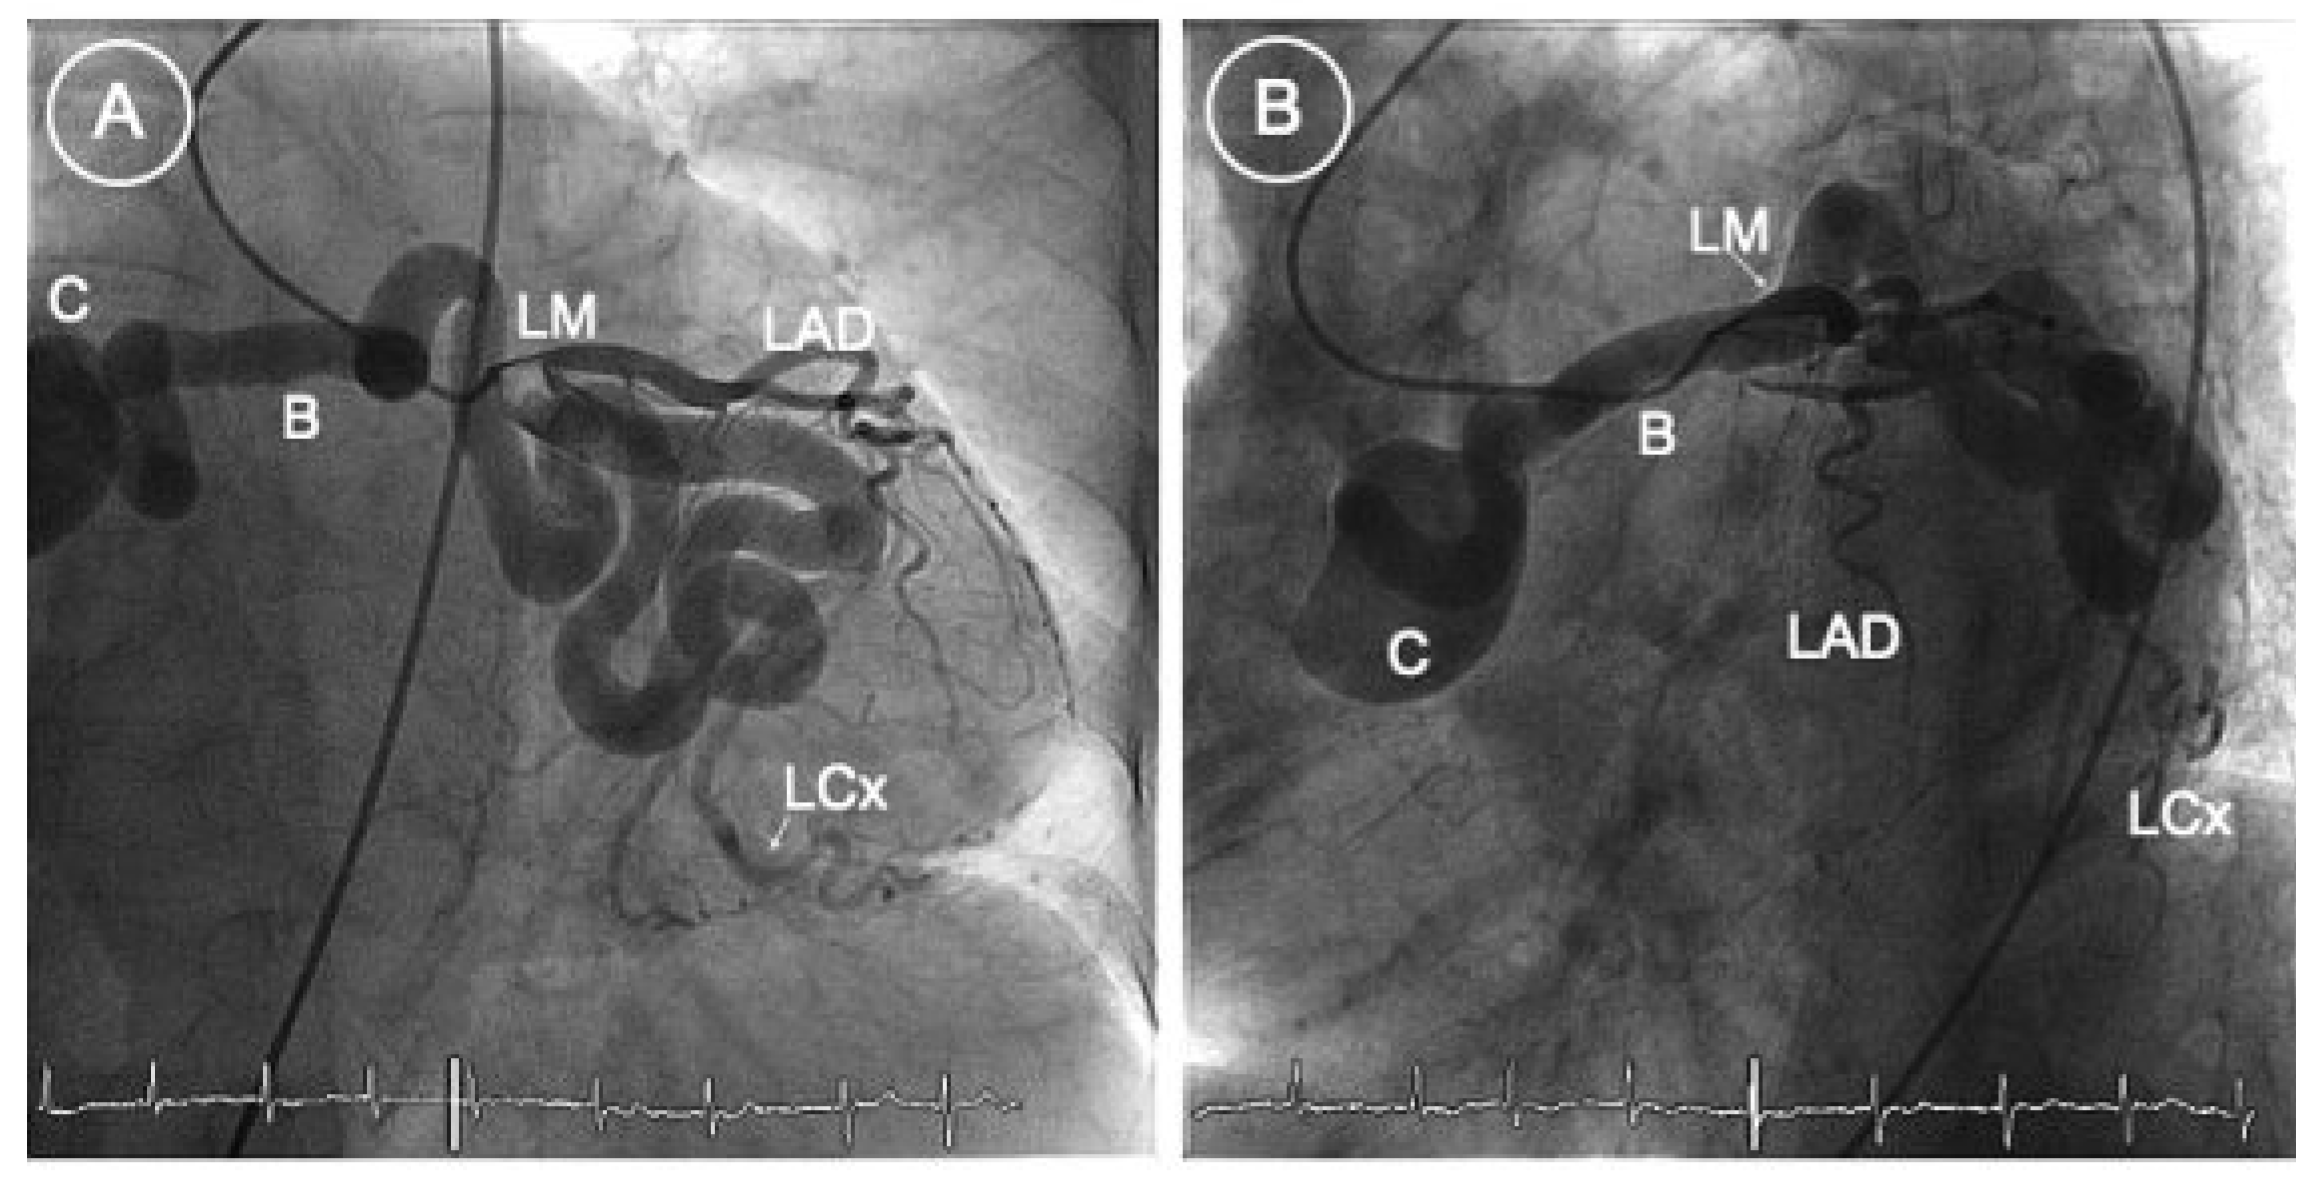

It was considered that the symptoms were at least in part triggered by the coronary fistula. A 6 Fr EBU 4.0 guiding catheter was therefore used to selectively engage the left main stem. The fistula was cannulated with a Fathom (Boston Sci) steerable guidewire (0.016″). Using a Renegade STC 18 microcatheter, and five 2D Interlock coils (Boston Sci; 10 mm × 30 cm, 4 × 8 mm × 20 cm) were deployed within the fistula and successfully clogged the visible blood flow within it (Figure 2B and Figure 3). There were no periprocedural complications and the patient was discharged the following day with a lifelong prescription of aspirin. The risk of atrial fibrillation-related ischaemic stroke was mild (CHADs score of 1 point—2.8%/year) but—mainly due to the patient’s age—the risk of bleeding was high (CRUSADE bleeding risk was 54 points—14%/month). Therefore, and in order to allow complete and definitive closure of the fistula, oral anticoagulation was discontinued for one month. Three months post procedure the patient remained free of symptoms.

Figure 2.

RAO (A) and anteroposterior (B) caudal views showing the deployment of coils within the fistula. Successful reduction of bloodflow within the fistula (B). LM = left main coronary artery; LAD = left anterior descending artery; LCx = left circumflex artery.

Figure 3.

Anteroposterior view. End result after deployment of 5 coils. LM = left main coronary artery; LAD = left anterior descending artery; LCx = left circumflex artery.